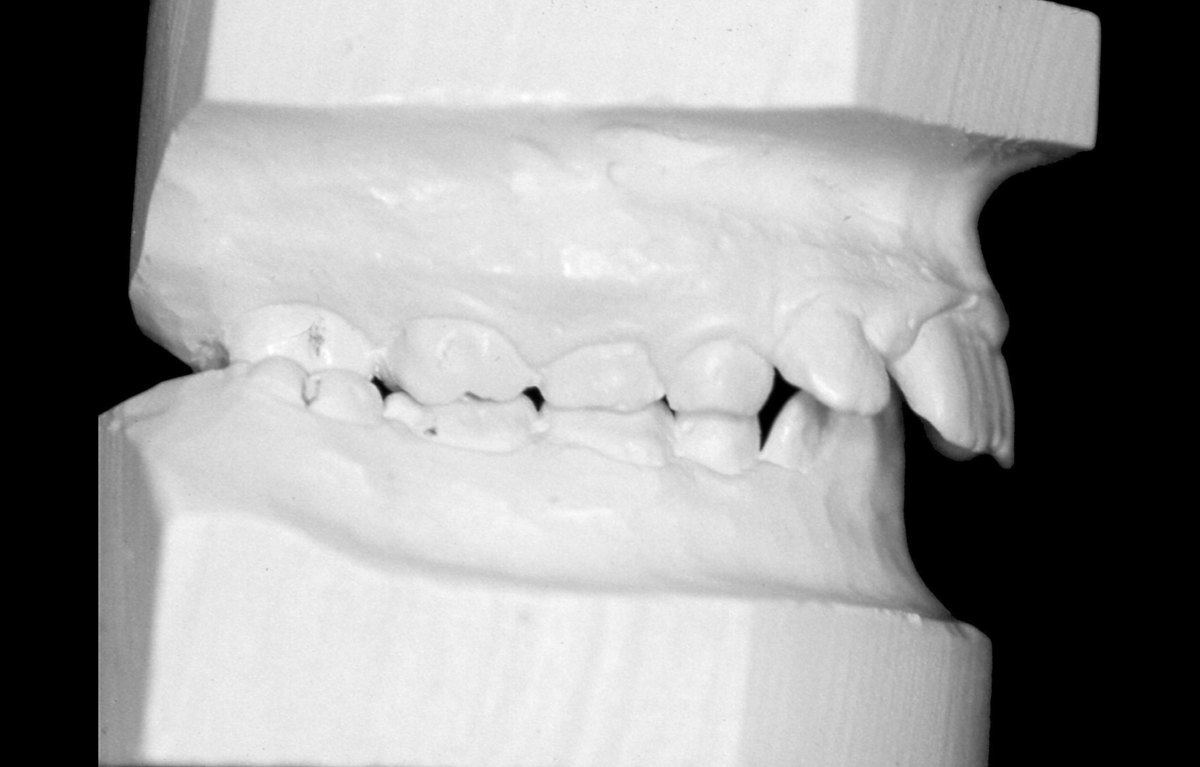

Наскоро излезе книгата на д-р Мишел Монто Нашите зъби - портал към здравето. Д-р Татяна Тасева, медицински консултант на книгата, любезно се съгласи да отговори на няколко въпроса. Защо книгата не е това, което изглежда; как мъдростта на зъбите (дентософията) може да промени целия живот на човека – вече и в България; как психоемоционалното състояние зависи от хармонията в устата и още можете да прочетете тук.

От баланса на нашите зъби зависят психичното здраве и емоционалният ни комфорт (интервю)